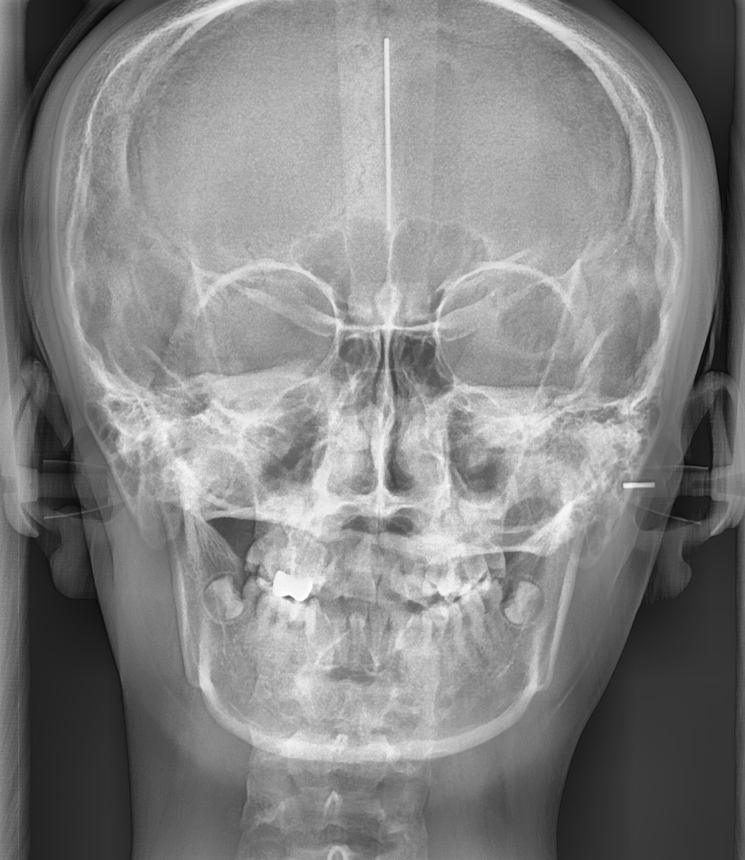

발치 여부는 환자의 치아 상태, 골격 구조, 교합 상태

복합적으로 고려하여 결정해야해요~

정확한 진단을 위해 X-RAY와 구강 내 사진을 많이 찍게 되는데

환자분들께 조금 힘드시더라도

만족스러운 교정을 위한 과정이니 양해 부탁드립니다!!!